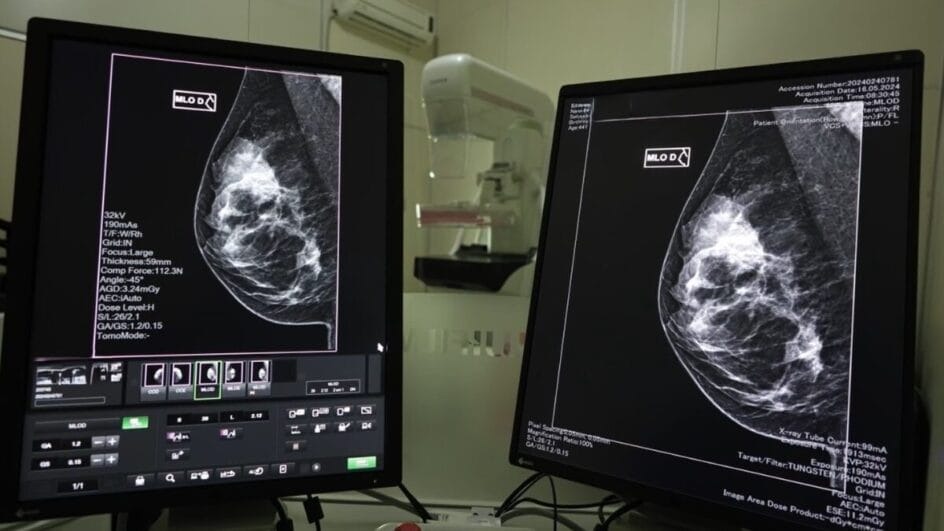

Em celebração ao Dia Internacional da Mulher, o governo de Santa Catarina, por meio da Secretaria de Estado da Saúde (SES), promoverá um mutirão de mamografias com prioridade para pacientes que estão na fila de espera do Sistema Nacional de Regulação (Sisreg). O anúncio foi feito no último sábado (8) e visa facilitar o acesso das mulheres ao diagnóstico precoce do câncer de mama, uma das principais ações do Estado no mês de março.

Em 2024, Santa Catarina registrou mais de 2,5 mil diagnósticos de câncer de mama e realizou 167,2 mil mamografias pelo Sistema Único de Saúde (SUS). O diagnóstico precoce é essencial para aumentar as chances de tratamentos menos invasivos e com melhores taxas de sucesso. As mamografias são realizadas principalmente pela Atenção Primária à Saúde, com apoio dos consórcios municipais e prestadores de serviços nos municípios.

As unidades estaduais de saúde que possuem mamógrafos também realizarão exames. O SUS oferece acesso gratuito a exames, internações e medicamentos para mulheres em todas as fases do tratamento.